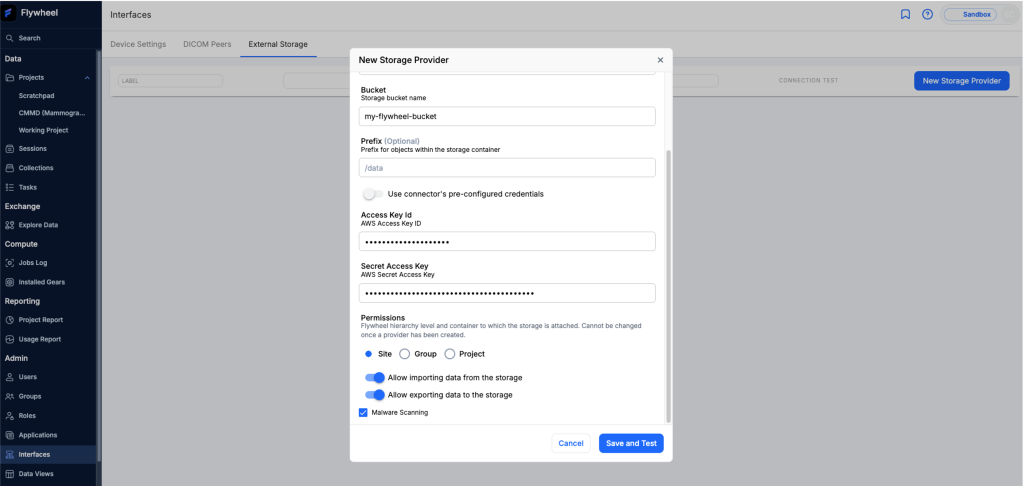

Amazon S3 scales effortlessly, handle growing data with performance. As with all health data, security is essential, Amazon S3 is HIPAA eligible and provides enhanced encryption features, access controls and audit logging to help maintain data integrity and compliance with regulations. Through Flywheel’s Interfaces tab, you can mount multiple Amazon S3 buckets onto Flywheel for data import, export, or both with a click of a button.

To enable secure access to your medical imaging data, you can connect your Amazon S3 bucket to Flywheel by configuring AWS credentials. First, specify your S3 bucket (for example, s3://my-flywheel-bucket) in the Flywheel interface. Then, provide the AWS Access Key and Secret Access Key associated with an AWS Identify and Access Management (IAM) role that has appropriate permissions to access the bucket. This configuration, illustrated in Figure 2, establishes a secure connection between Flywheel and your S3 storage.

Figure 2 – Add S3 Storage Provider